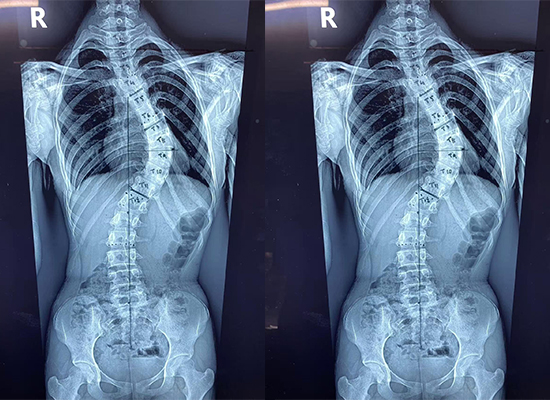

В этом случае процедура коррекции сколиоза была успешно проведена в местной ортопедической больнице в Дакке, Бангладеш , с участием 14-летней пациентки с диагнозом подростковый сколиоз. Целью хирургического вмешательства была коррекция деформации позвоночника, восстановление выравнивания и достижение стабильной внутренней фиксации с использованием системы транспедикулярных винтов и стержней диаметром 6,0 мм..

Послеоперационная визуализация продемонстрировала улучшение выравнивания позвоночника по сравнению с дооперационным состоянием. Фиксирующая конструкция оказалась стабильной, поддерживая запланированную коррекцию. По словам хирургической бригады, у пациента наблюдалось удовлетворительное послеоперационное восстановление, без каких-либо немедленных осложнений, связанных с фиксацией.

Выравнивание позвоночника оценивалось с помощью визуализирующих исследований перед операцией и послеоперационных рентгенографических исследований для подтверждения коррекции и стабильности фиксации.

Послеоперационная визуализация показала улучшение выравнивания позвоночника, и пациент продемонстрировал удовлетворительное выздоровление со стабильной внутренней фиксацией.